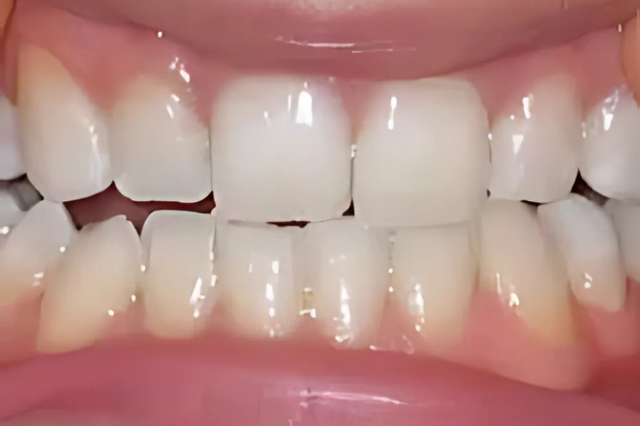

Utána

Előtte